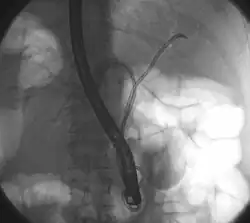

| Klatskin tumor during ERCP. Wires were inserted into the left and right biliary systems. Both parts were injected through a tube with contrast, but there is no contrast visible in the area of confluence of the two systems | |